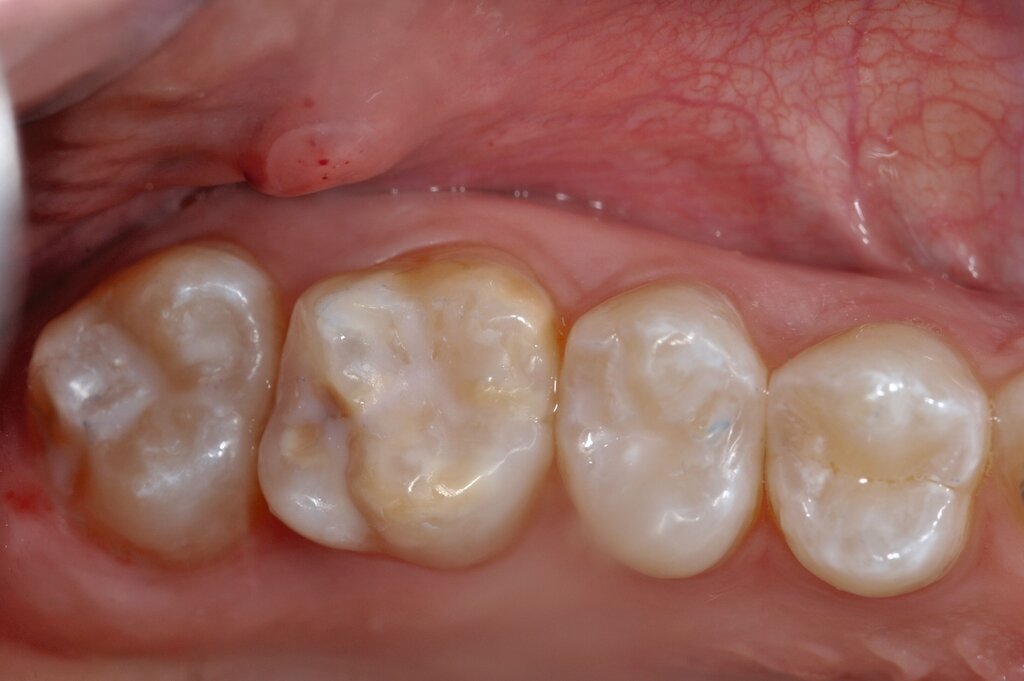

Die definitive Versorgung der MIH-affektierten Molaren und Frontzähne umfasst die adhäsive Versorgung direkt mit Komposit oder indirekt mit Keramik oder Komposit.

Die direkte Versorgung mit Komposit hat den Vorteil, dass durch die Verwendung von Dentinadhäsiven das Dentin dicht versiegelt werden kann. Hypersensitivitäten werden dadurch deutlich reduziert. Zudem kann der Zahn bei der direkten Versorgung sehr defektorientiert versorgt werden (Abbildung 7).

Während die Dentinhaftung unterhalb des affektierten Schmelzes vergleichbar mit der von gesundem Dentin ist, funktioniert die Haftung an dem strukturell veränderten Schmelz schlechter. Eigene Untersuchungen haben gezeigt, dass die Haftung an dem porösen, proteinreichen Schmelz stark reduziert ist (Abbildung 8) [Krämer et al., 2018]. Sind die Füllungsränder in dem veränderten Bereich lokalisiert, muss mit Randspalten und Abplatzungen gerechnet werden.

Bei größeren Restaurationen muss man im Laufe der Jahre mit Verfärbungen der Füllungen und mit Abrasionen rechnen. Dies spielt insbesondere eine Rolle, wenn im Seitenzahnbereich Höcker ersetzt werden müssen, da Kompositfüllungen mit Höckerersatz an MIH-Molaren eine etwas geringere durchschnittliche Überlebenszeit in der Mundhöhle haben als solche ohne Höckerrekonstruktion [Rolim et al., 2021].

Die Anzahl der klinischen Studien zur direkten adhäsiven Versorgung an MIH-Molaren ist begrenzt, so dass nur bedingt Aussagen zur Erfolgsrate getroffen werden können. So zeigten Linner et al. [2020], dass konventionelle direkte Kompositfüllungen eine kumulative Überlebensrate von rund 76 Prozent nach drei Jahren aufwiesen, die zwischen der von indirekten Keramikrestaurationen (100 Prozent) und GIZ-Füllungen (7 Prozent) lag [Linner et al., 2020].

Ähnliche Überlebensraten berichteten auch Rolim et al. [2021] für direkte Kompositfüllungen an MIH-Zähnen, die bei der Verwendung eines Universaladhäsivs in Etch-and-Rinse Technik bei 80,8 Prozent und in Self-Etch Technik bei 62,3 Prozent nach zwölf Monaten lagen [Rolim et al., 2021]. Wenngleich dies positive Ergebnisse hinsichtlich des kurz- und mittelfristigen Erfolgs direkter Kompositfüllungen bei MIH-Molaren sind, bleibt zu berücksichtigen, dass es weiteren Forschungsbedarf zur Bestimmung des Langzeiterfolgs dieser restaurativen Maßnahme gibt [Lygidakis et al., 2022].